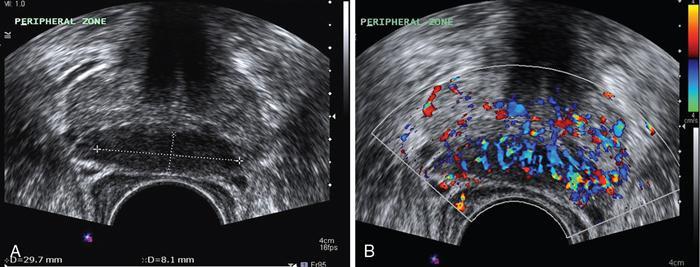

Prostatitis